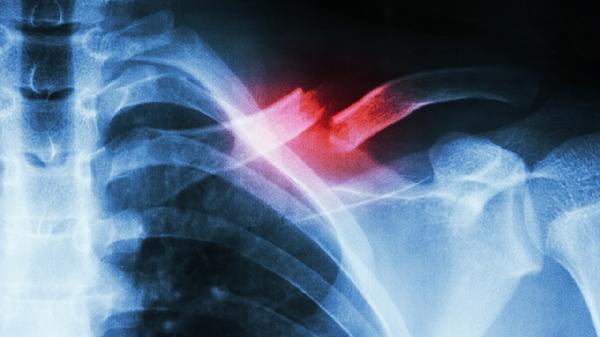

肋软骨炎应该注意事项有哪些

肋软骨炎需注意避免胸壁受压、控制炎症反应、调整呼吸方式、适度功能锻炼及预防复发。肋软骨炎的处理需结合日常生活管理与医疗干预,主要注意事项有避免胸壁受压、控制炎症反应、调整呼吸方式、适度功能锻炼及预防复发。